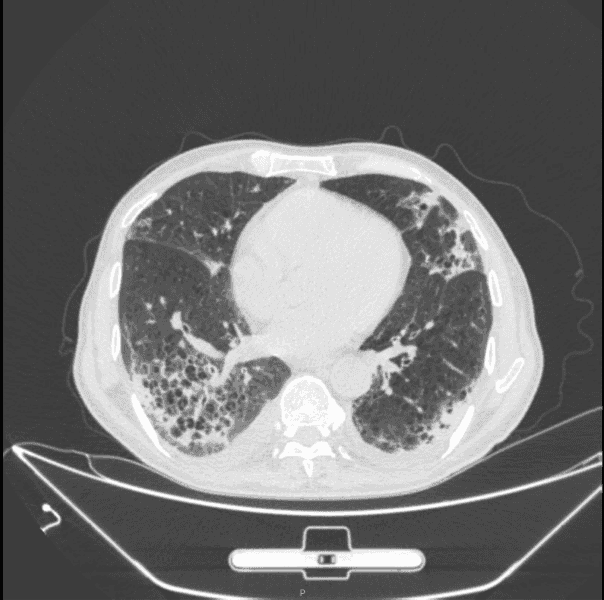

胸部 CT: 两肺间质性炎症,两肺肺气肿(图 3)。

图 3:出院第二十天胸部 CT,两肺间质性炎症,两肺肺气肿患者目前无发热畏寒,无咳嗽咳痰,偶有胸闷气喘,无头晕头痛,无心慌气促,无恶心呕吐,神志清,精神可,饮食睡眠可,大小便正常,体重近期无明显改变案例总结:

所有治疗衣原体的方法相似本例患者主要采用注射用哌拉西林钠他唑巴坦钠和莫西沙星治疗,治疗两周后感染指标明显控制,临床症状明显改善患者因为检测出乙肝小三阳和梅毒特异性抗体阳性,因此前往传染病医院进一步治疗,我们让患者出院后继续口服克拉霉素和莫西沙星,并且在出院的第二十天进行复查,发现患者的实验室各项指标都在明显好转,没有阳性临床症状,CT 也提示较前明显好转,但是患者还没有得到完全恢复,推测可能与患者免疫功能低下有关,我们会对该患者进行后续随访。